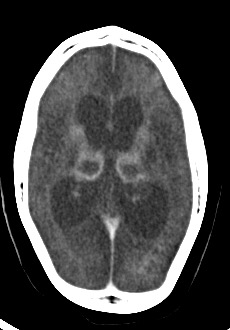

脳組織のびまん性の萎縮が認められる

• 頭部は脳組織のびまん性の萎縮が認められる。両側大脳半球は多嚢胞性脳軟化症の状態。両側の基底核、視床、中脳、橋、延髄、小脳とも強い低吸収化で軟化と萎縮を示す。

• 両側の中大脳動脈や脳底動脈は非常に細く、需要減少に伴う脳血流低下を示す所見と思われる。

• 急性期の異常所見は、あったとしても指摘が困難であろうが、少なくとも大量の出血や左右差をもたらす様な所見は生じていない。

• 両側基底核の嚢胞状変化は留意すべき所見かもしれない。顔面頭蓋部分でも筋萎縮が著しい。眼窩内容も外眼筋が非常に細く、脂肪組織が非常に優越している。頭蓋骨肥厚、眼窩が相対的に非常に大きく見えているのは脳萎縮に伴うものであろう。